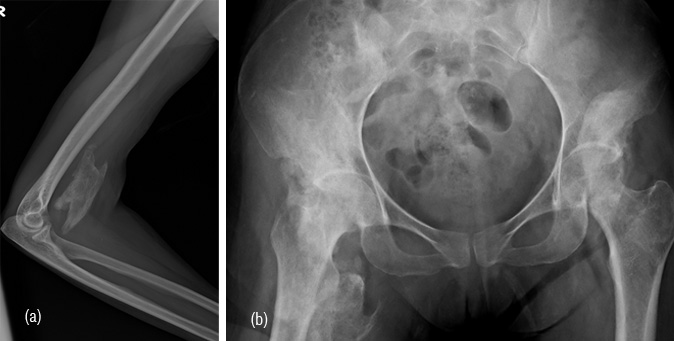

Granulomas

Langerhan’s histiocytosis X is commonly encoutered in children. However, a solitary lesion eg., eosinophilic granuloma may also be seen in adults. Radiologically, eosinophilic granuloma is a solitary lytic lesion in the medulla of a long bone with endosteal scalloping. It may break the cortex and produce periosteal reaction (Figure 11a). When lytic it may simulate metastasis (Figure 11b). In the skull, the edges of the lytic lesion may have a bevelled edges (Figure 11c). In Hand Shuller Christian type of histiocytosis which is encoutered in young adults associated with enlargement of liver and spleen, bone lesions are multiple and may simulate lymphoma or metastasis (Figure 11d).

Figure 11: (a) Eosinophilic granuloma in femur, (b) Metastasis from bronchogenic carcinoma, (c) Large eosinophilic granuloma in skull, (d) Langerhan’s histiocytosis X in iliac bone with multiple lytic lesions.